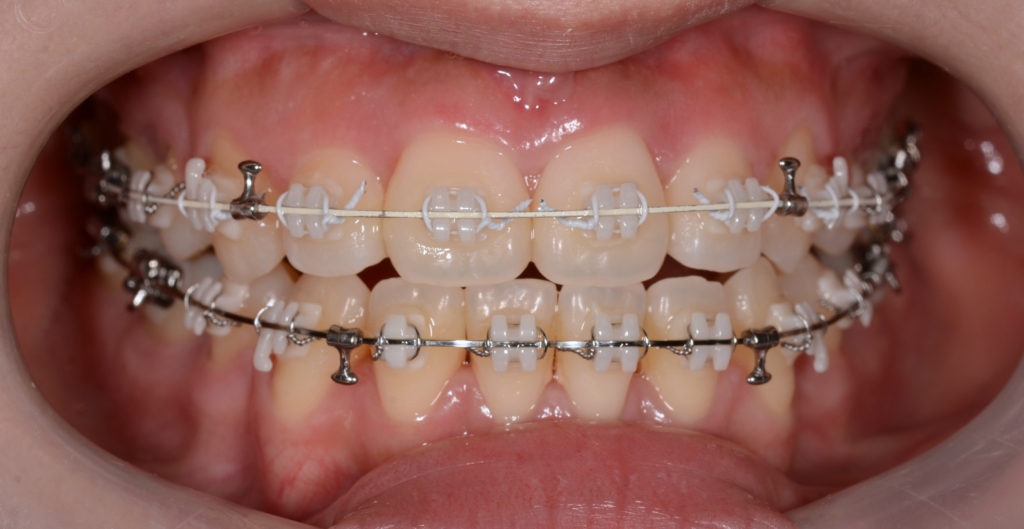

マルチブラケットシステム(ハーフホワイトtype)で矯正を開始。

順当に矯正治療は進んで、前歯を奥へ引っ込めるステップに入りました。

上下とも前歯を奥へ出来るだけたくさん引っ込めるよう治療を進めます。

ハーフホワイトtypeのマルチブラケットシステム

アンカースクリューを2本